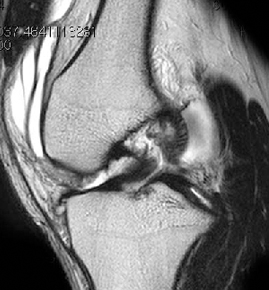

• ACL 손상 방사선 사진1